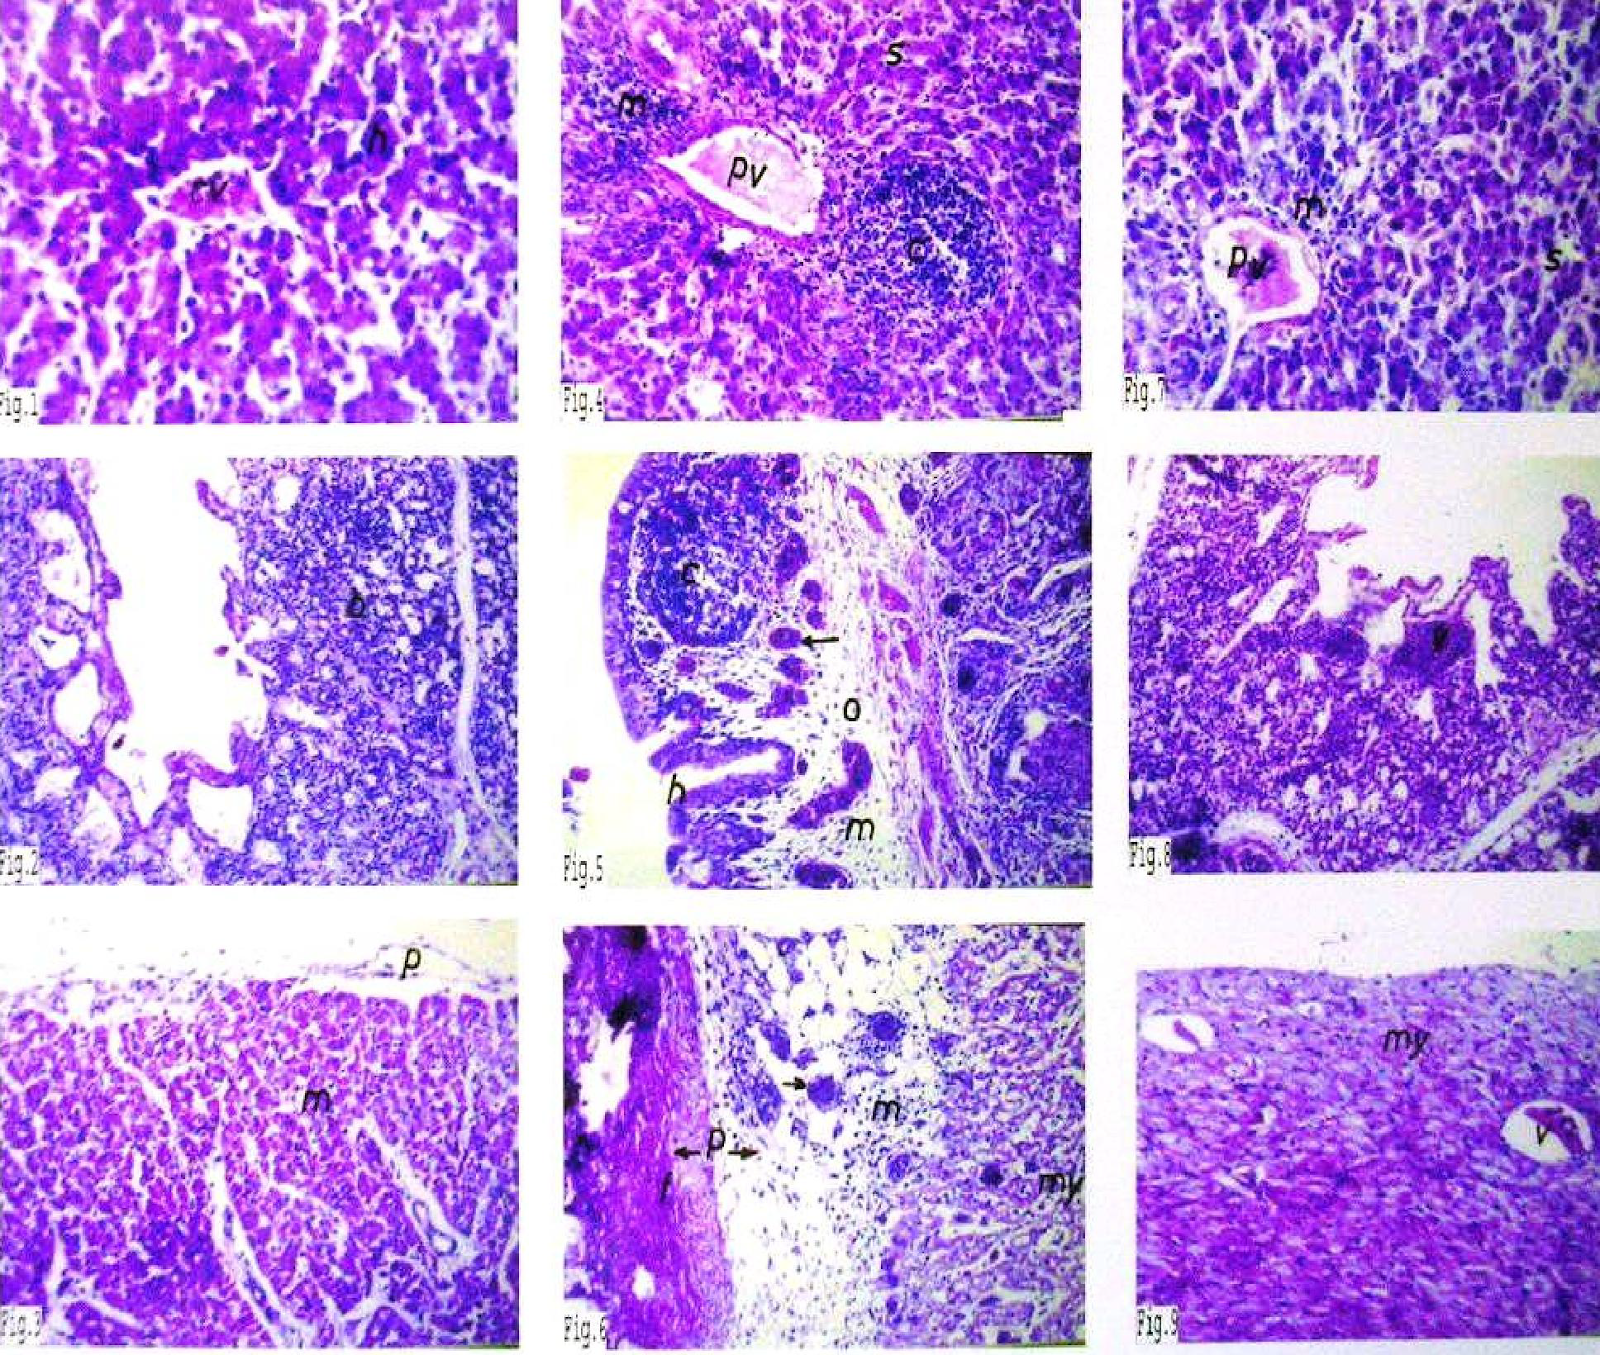

BAB IV HASIL DAN PEMBAHASAN A. Identifikasi E. coli Berdasarkan penelitian yang telah dilakukan dari 10 sampel feses yang diamb

PERTUMBUHAN BAKTERI E.coli DAN Bacillus subtilis PADA MEDIA SINGKONG, UBI JALAR PUTIH, DAN UBI JALAR KUNING SEBAGAI SUBSTITUSI

IDENTIFIKASI BAKTERI Escherichia coli DAN Shigella sp. TERHADAP JAJANAN CILOK PADA LINGKUNGAN SD NEGERI DI CIRENDEU, PISANGAN, DAN CEMPAKA PUTIH - PDF Free Download

Analis Kesehatan Indonesia: Kultur dan Hasil Uji Biokimia Bakteri Gram Negatif

Identifikasi Bakteri Staphylococcus aureus dan Jamur Helminthosporium sp | mulyadiveterinary